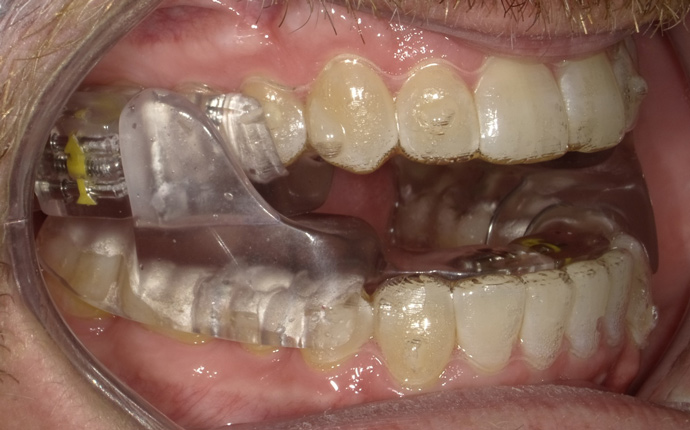

Intraoral scans were taken to document the patient's entire palate and bite registration. Scans were sent to the clinical team for the fabrication of a clear aligner/sleep appliance for the patient to wear; the chosen appliance fits over clear aligners, regardless of the tray number the patient may need (Figure 7 through Figure 11).

After the appliance was delivered, additional photographs were taken with the camera to ensure that the appliance was delivered as intended, to document the case, and to show the patient the ideal fit of the appliance in his mouth as instructions were reviewed with him.

Fig 8. The appliance worn during treatment, anterior view (Fig 8), right side view (Fig 9), left side view (Fig 10), and upper arch view (Fig 11).

Figure 8

Fig 9. The appliance worn during treatment, anterior view (Fig 8), right side view (Fig 9), left side view (Fig 10), and upper arch view (Fig 11).

Figure 9

Fig 10. The appliance worn during treatment, anterior view (Fig 8), right side view (Fig 9), left side view (Fig 10), and upper arch view (Fig 11).

Figure 10

Fig 11. The appliance worn during treatment, anterior view (Fig 8), right side view (Fig 9), left side view (Fig 10), and upper arch view (Fig 11).

Figure 11